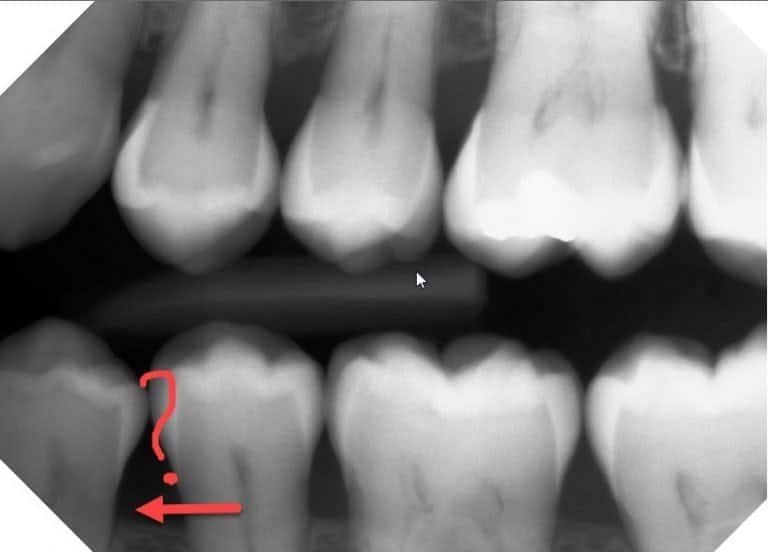

Pulp cells are found in the nerve chamber and canals inside the tooth. They start growing outward, turning the dentin into a sponge-like, soft, mushy mess. It’s usually a very slow process, and it’s rarely painful until it has progressed a lot. Because it usually happens in tooth roots, it’s often not visible on normal x-rays. That means dentists can’t see it, unless there’s a reason to take an x-ray of the whole tooth, as seen here. This was taken in July 2019, on a new patient in our practice. It became sensitive just recently.

Based on this x-ray alone, I didn’t know if this was internal or external resorption. So we took a 3D Cone Beam x-ray , to see it from multiple angles, as seen below. From that, it appears to be internal root resorption. It got big enough to break through the root, which allows bacteria in. That’s probably why it became sensitive recently.